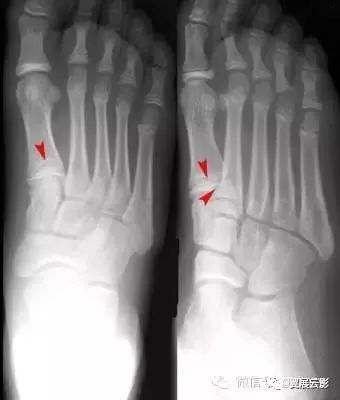

42张x线片带你读懂不同部位骨折

跖骨骨折